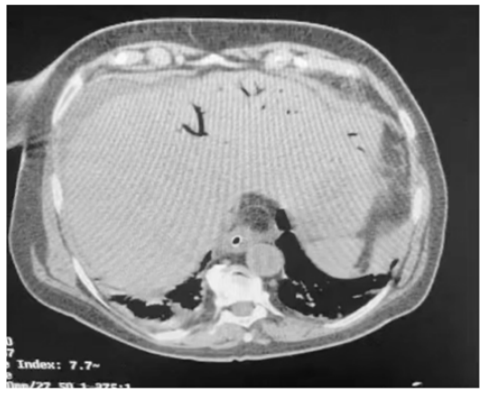

Um paciente de oitenta anos de idade, já com grau de perda de funcionalidade, com períodos de esquecimento, chegou ao pronto-socorro com queda importante do estado geral, com poucas informações objetivas, porém com dor ao exame físico de abdômen. Difícil interpretação dos sinais de irritação peritoneal. Realizou a tomografia abaixo.

A principal causa desse achado é o(a)